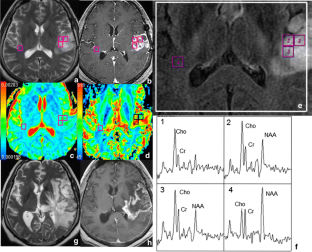

Fig. 2